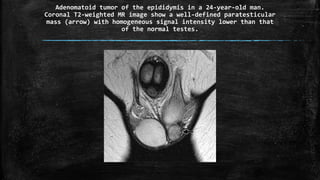

Adenomatoid tumor of the epididymis in a 24-year-old man.

Coronal T2-weighted MR image show a well-defined paratesticular

mass (arrow) with homogeneous signal intensity lower than that

of the normal testes.